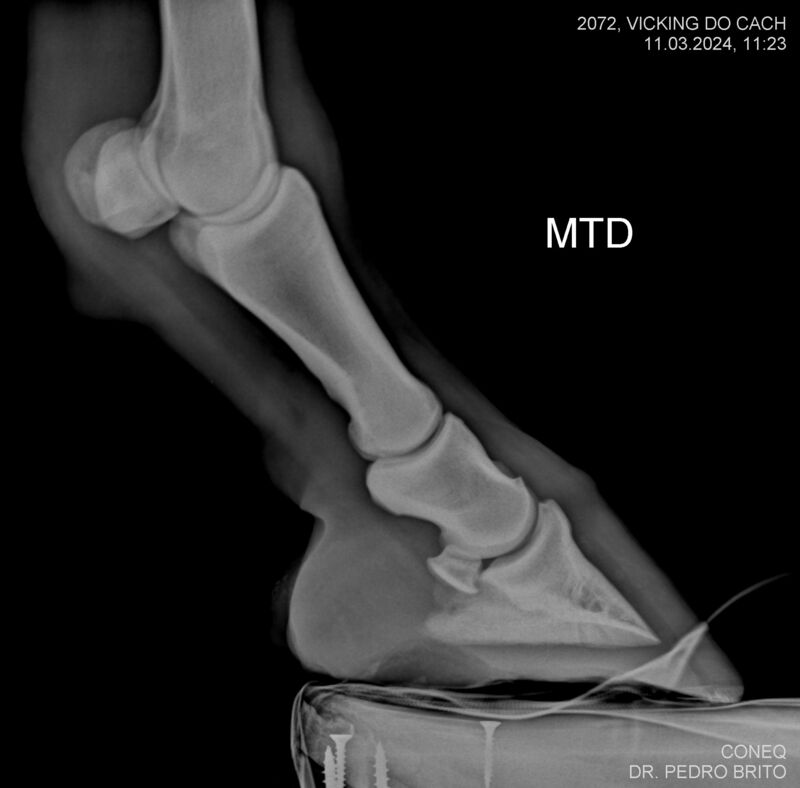

VIKING DO CACH